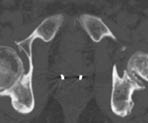

One week after transponder placement, a non-contrast CT scan, Figures 3a and 3b, is obtained under the supervision of the treating radiation oncologist according to the following parameters (FOV = 48 cm; matrix = 512 x 512): from 2 cm above the iliac crest to 2 cm above the femoral heads with 1 cm slice thickness; from 2 cm above the femoral heads to the bottom of the ischial tuberosities using 3 mm slice thickness; and from the bottom of the ischial tuberosities to 12 cm caudal using 1 cm slice thickness. The resultant images are transferred to a treatment planning workstation where a CT-MRI fusion is performed employing chamfer matching and maximization of mutual information techniques. Once the fusion is complete, the critical structures are contoured, including the prostatic fossa, bladder and rectum, as well as the femoral heads, skin and small bowel. The transponder beacons are also identified during this process and their location is registered by the software. An intensity-modulated radiation therapy (IMRT) plan is generated that will cover the planned target volume while limiting the dose to the bladder and rectum. The stored location of the beacons is where the transponders are expected to be found during daily RT treatments, and the Calypso system compares the expected location to the actual location of the transponders prior to the beginning of each treatment session. By convention, a greater than 5 mm intrafraction movement in any direction would result in a cessation of the daily fractionated dose and a realignment of the Calypso system. In order to realign the system, a repeat CT scan must be performed to re-contour the critical structures in relation to the new location of one of the transponders.

Figure 3a. Axial CT image of two electromagnetic transponder beacons in prostatic bed.